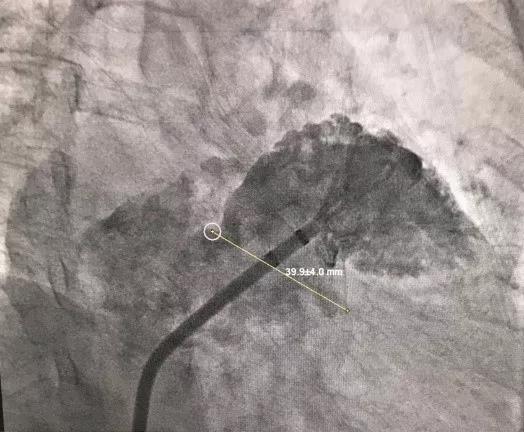

6月3日上午8点,由复旦大学附属中山医院向大会现场直播了一台选用LAmbre™左心耳封堵器系统进行的封堵手术。本例手术由复旦大学附属中山医院的周达新教授和来自香港的林逸贤教授共同完成。接受手术的患者为一名77岁男性,患者3个月前脑梗,并拒绝长期抗凝药物治疗,被诊断为心房颤动,入院评估CHA2DS2-VASc评分为5分。术中造影测量显示其左心耳开口直径为39.9mm,左心耳形态为风向标型。周达新教授和林逸贤教授决定选用型号为LT-LAA-3640的LAmbre™左心耳封堵器对患者实施封堵。手术进行的非常顺利,术后造影显示,患者左心耳封堵完全,无残余分流。

(术前造影)